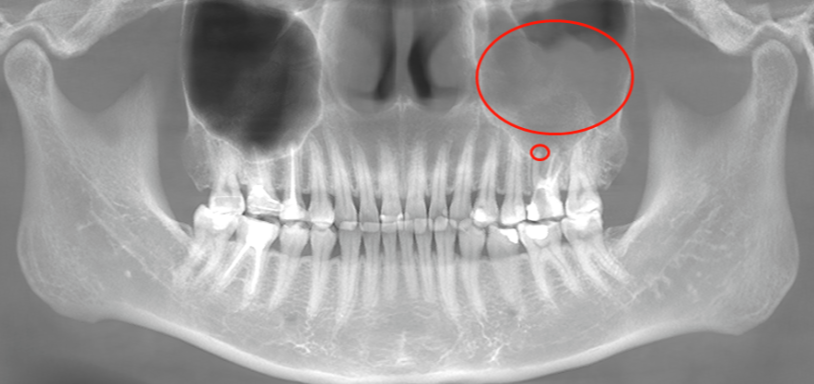

小牙片,能看单个牙齿或局部几颗牙,15元/次

曲面断层(全景牙片),查看全部牙及周围组织情况,85.5元/次

CBCT,对颌面部结构进行三维重建,精度最高,304元/次